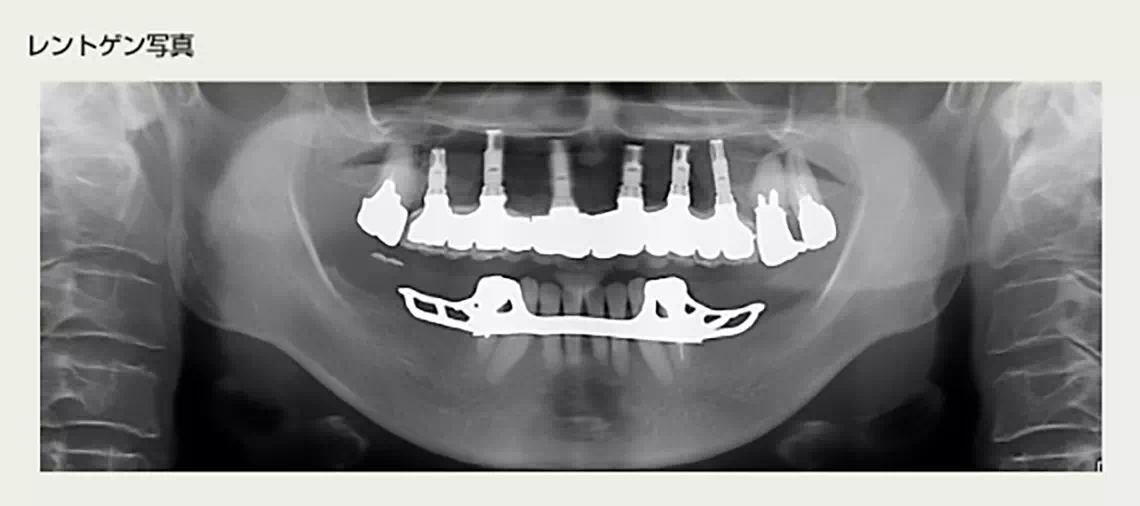

ほとんど歯の無い方 50代 女性

30代より徐々に歯がなくなり入れ歯にしていましたが、発音によっては入れ歯がはずれてしまい困っていました。インプラントで外れない綺麗な歯が欲しいという要望で、上顎にインプラント治療を行うことになりました。